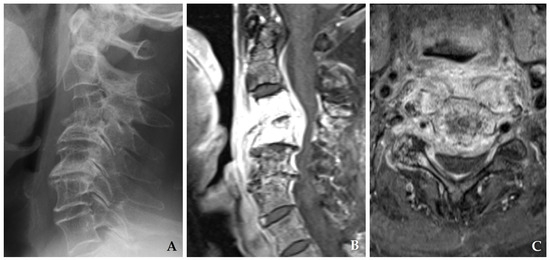

Necessary for extensive two-column disease, severe kyphosis, or multilevel vertebral collapse. While associated with greater operative morbidity, it provides comprehensive decompression and 360° stabilization, making it the optimal choice for complex or refractory infections (Figure 5) [37,38].

Figure 5. Initial magnetic resonance imaging (A) demonstrates disc space narrowing at C4–C5 and a large epidural abscess causing spinal cord compression. The patient underwent C4–C6 corpectomy with autograft and anterior plating (B), achieving solid fusion and complete resolution of spondylodiscitis at six months postoperatively (C).